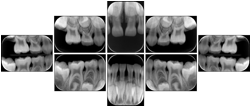

Intra-oral radiography typically involves acquisition of multiple images of various parts of the dentition. Many digital radiographic systems offer customized templates that are used for displaying the images in a study on the screen. These templates may also be referred to as mounts or view sets. The Structured Display Object represents a standard method of encoding and exchanging the layout and intended display of Structured Displays. A structured display object created in this manner could be stored with a study and exchanged with images to allow for complete reproduction of the original exam.

In most standard cases, images are oriented in structured layouts. These structured displays are useful to be shared between providers for reference purposes.

Table OO.1.1-1 shows structured display standard templates, where Viewset ID is based on the Japanese Society for Oral and Maxillofacial Radiology (JSOMR) classification provided by JIRA (Japan Medical Imaging and Radiological Systems Industries Association, www.jira-net.or.jp). Expected or typical teeth to be imaged location, region and designation codes are based on ISO 3950-2010, Dentistry - Designation system for teeth and areas of the oral cavity. For all the hanging protocols listed in OO.1.1-1, the value to use for Hanging Protocol Creator (0072,0008) is "JSOMR" and the value to use for Hanging Protocol Name (0072,0002) does not include "JSOMR" (e.g., "DL-S001A", not "JSOMR DL-S001A").